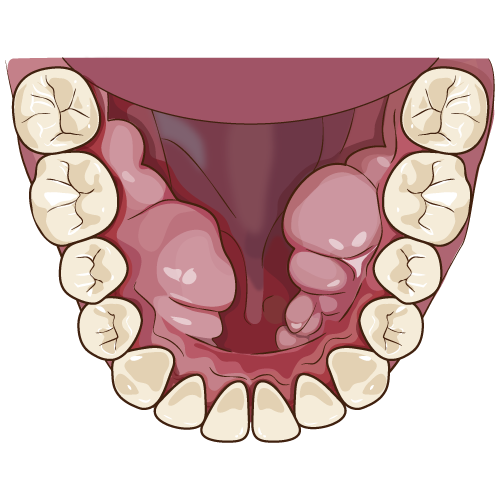

智歯周囲炎とは親知らずがうまく生えることができず、その周りに細菌が感染し炎症が起こっている状態。

奥歯周囲をよく磨くようにし、市販の痛み止め化膿止めを飲むようにしましょう。